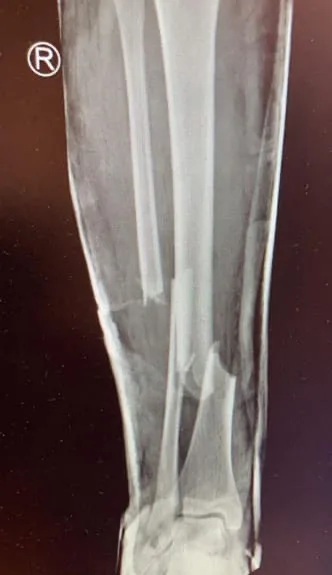

As he touched my right shin, where my bone had snapped, I wailed in agony.

There, X-rays revealed I’d broken my right leg, had a 3cm hole in my mouth, missing teeth, a smashed jawbone, three broken ribs, dislocated collarbone, broken wrist, lacerated spleen and a punctured lung.